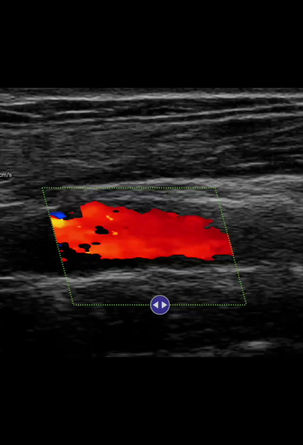

Thyroid Cyst

Apache neo L154 scanned with iPad Air (4th generation). Portrait mode.